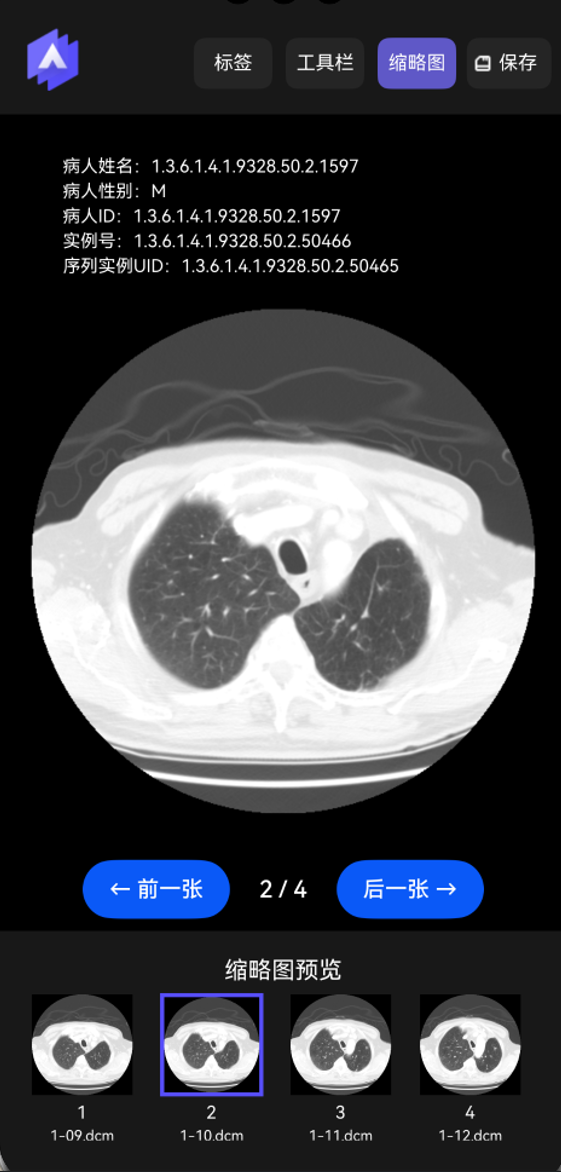

显示缩略图。打开序列后可以列表方式显示序列的缩略图,方便浏览查看,如下图所示。